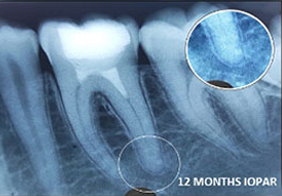

A case of combined REP in one Root and VPT in another Root.

Wound in bone (marked) in one root has healed through REP which is revealed in 6 and 12 months follow up IOPAR, the unaffected pulp in another Root Canal is protected through VPT resulting in the maintenance of validity of Tooth.